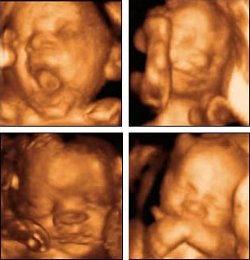

Abby Johnson trabajó durante ocho años para Planned Parenthood, la gran organización no gubernamental norteamericana defensora del aborto y la planificación de la natalidad. Esta entidad, utilizando el eufemismo de «salud reproductiva», promueve el aborto en Estados Unidos y en todo el mundo, favoreciendo la aprobación de leyes y políticas de liberalización de su práctica y presionando a los países que lo prohíben. La organización, fundada en los años veinte por Margaret Sanger, tiene un presupuesto de unos mil millones de dólares anuales y realiza directamente más de trescientos mil abortos al año. Johnson fue Directora Ejecutiva de la Clínica Bryan de Planned Parenthood, en Texas, durante dos años. Sin embargo, decidió presentar su dimisión tras contemplar una ecografía de un procedimiento abortista. Las imágenes, obtenidas mediante ultrasonidos, la conmovieron profundamente y pensó: «no puedo seguir haciendo esto».

(Bruno Moreno/InfoCatólica) No es la primera vez que la posibilidad de contemplar lo que en realidad está sucediendo cuando se provoca un aborto ha hecho que un abortista convencido cambie radicalmente de opinión sobre este tema. De hecho, uno de los grandes objetivos de los grupos pro-vida en Estados Unidos consiste en establecer la obligación legal de que cada mujer que quiera abortar vea primero unas imágenes por ultrasonidos del feto que quiere abortar. Previsiblemente, los defensores del aborto no son partidarios de ofrecer esa información a las mujeres que acuden a sus clínicas.